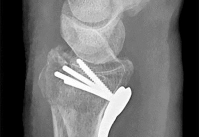

Question 7:

A 45-year-old trauma patient sustains an intra-articular distal femur fracture. Advanced imaging identifies a coronal plane fracture of the lateral femoral condyle (Hoffa fragment). Biomechanical studies suggest which of the following screw orientations provides the most rigid fixation for this specific fracture pattern?

Correct Answer: Posteroanterior oriented lag screws

Explanation:

A Hoffa fracture is a coronal plane fracture of the femoral condyle, more commonly affecting the lateral condyle. Biomechanical studies have demonstrated that posteroanterior (PA) directed lag screws provide superior stability and higher load to failure compared to anteroposterior (AP) directed screws. While AP screws are often used clinically due to ease of placement via an anterior approach, PA screws are biomechanically advantageous because they enter through thicker cortical bone posteriorly and are directed perpendicular to the fracture plane.